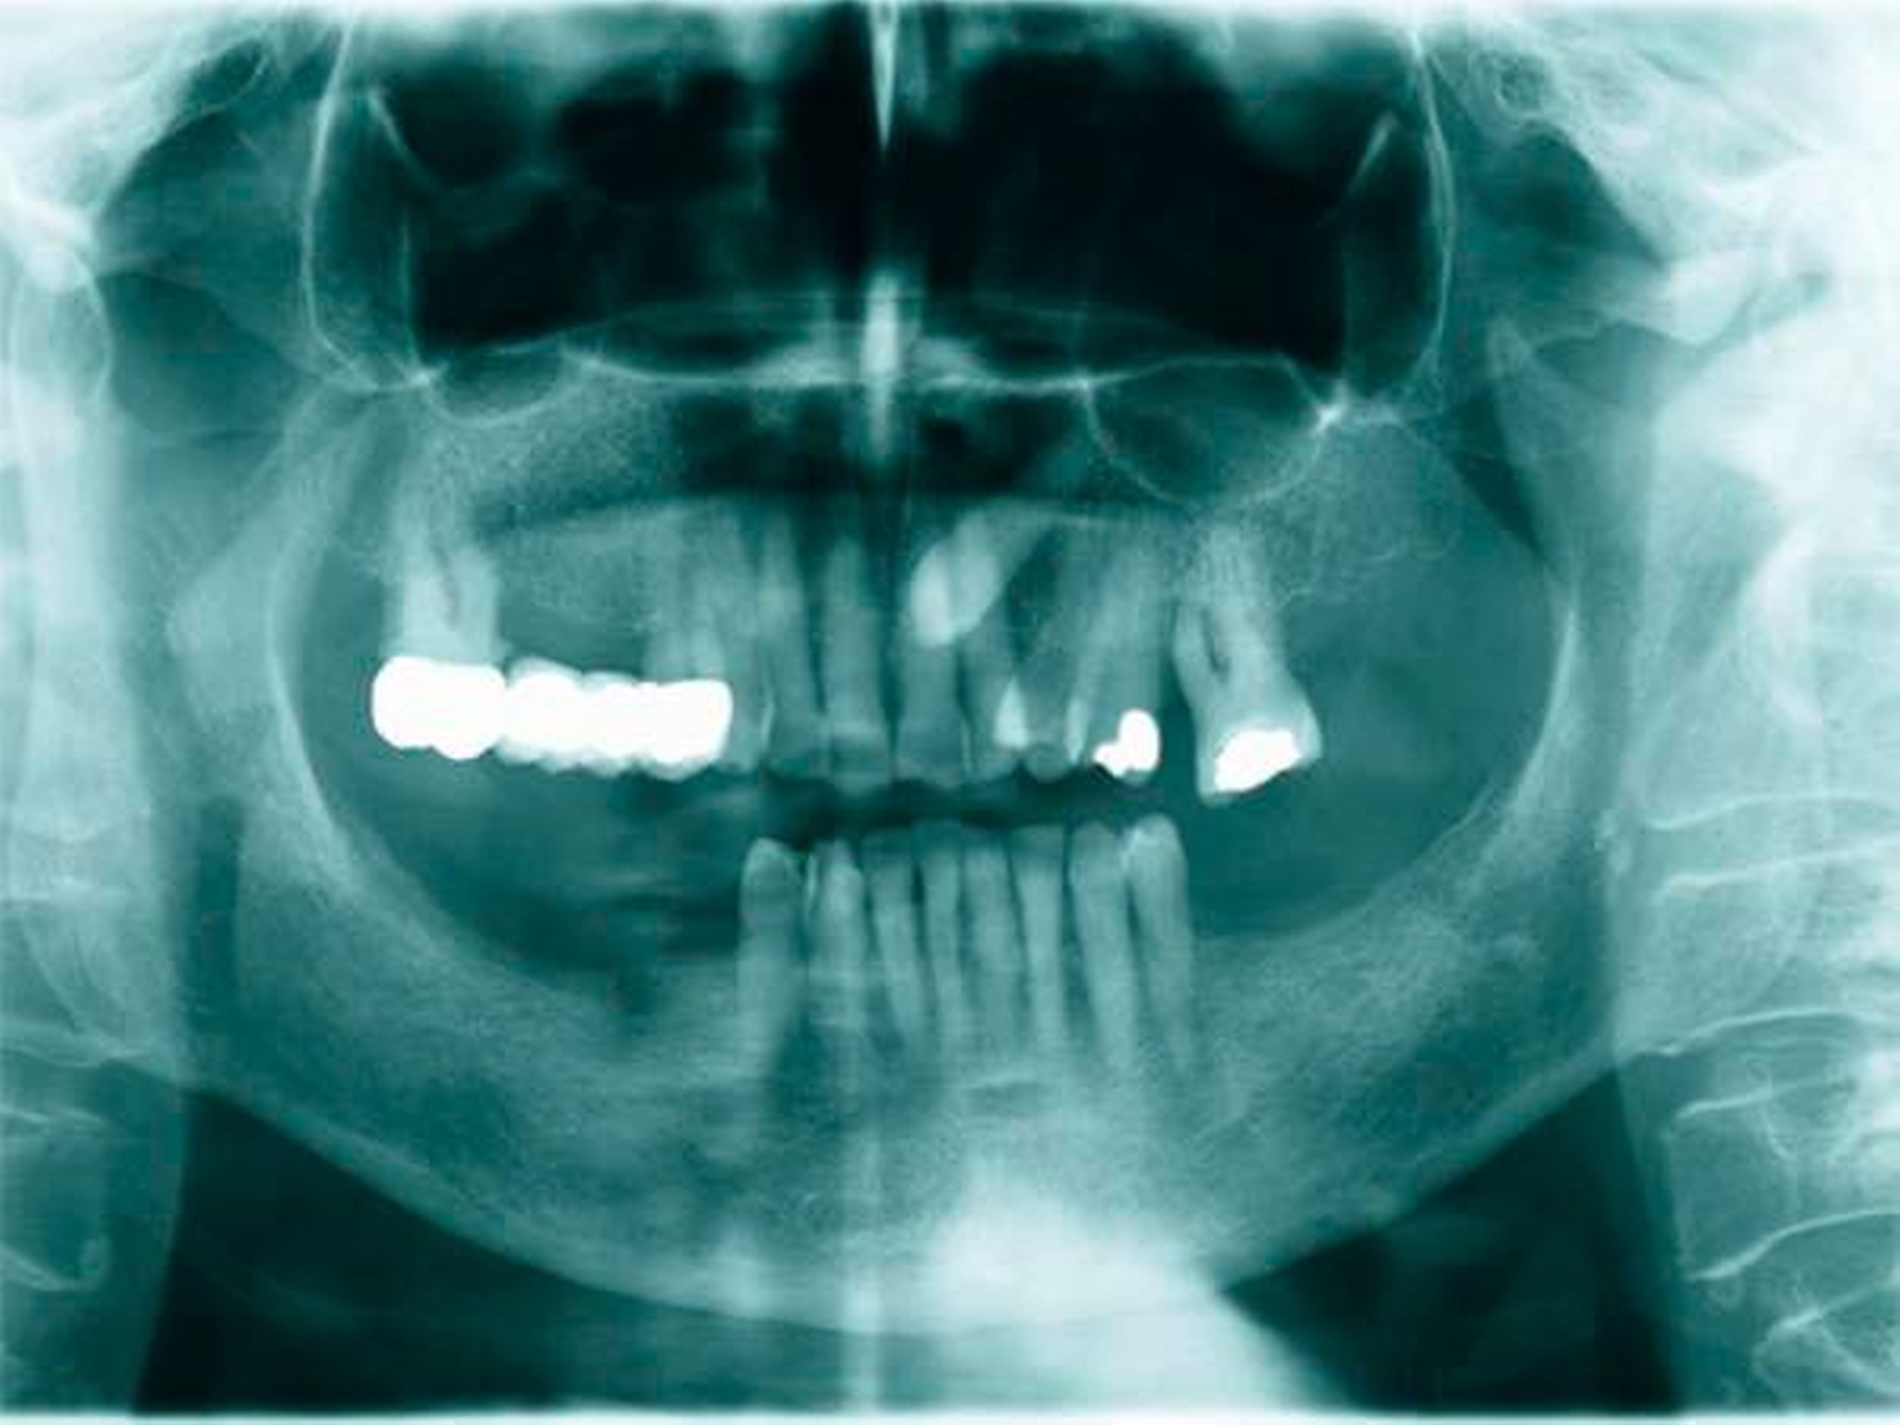

Aufgrund der schmerzhaften Gingivitis hatte die Patientin zudem Probleme mit der Nahrungsaufnahme. In der Panoramaschichtaufnahme (Abbildung 3) zeigte sich neben einem impaktierten Eckzahn ein Furkationsbefall der Molaren mit Konkrementen sowie ein altersentsprechender, generalisierter horizontaler Knochenabbau.